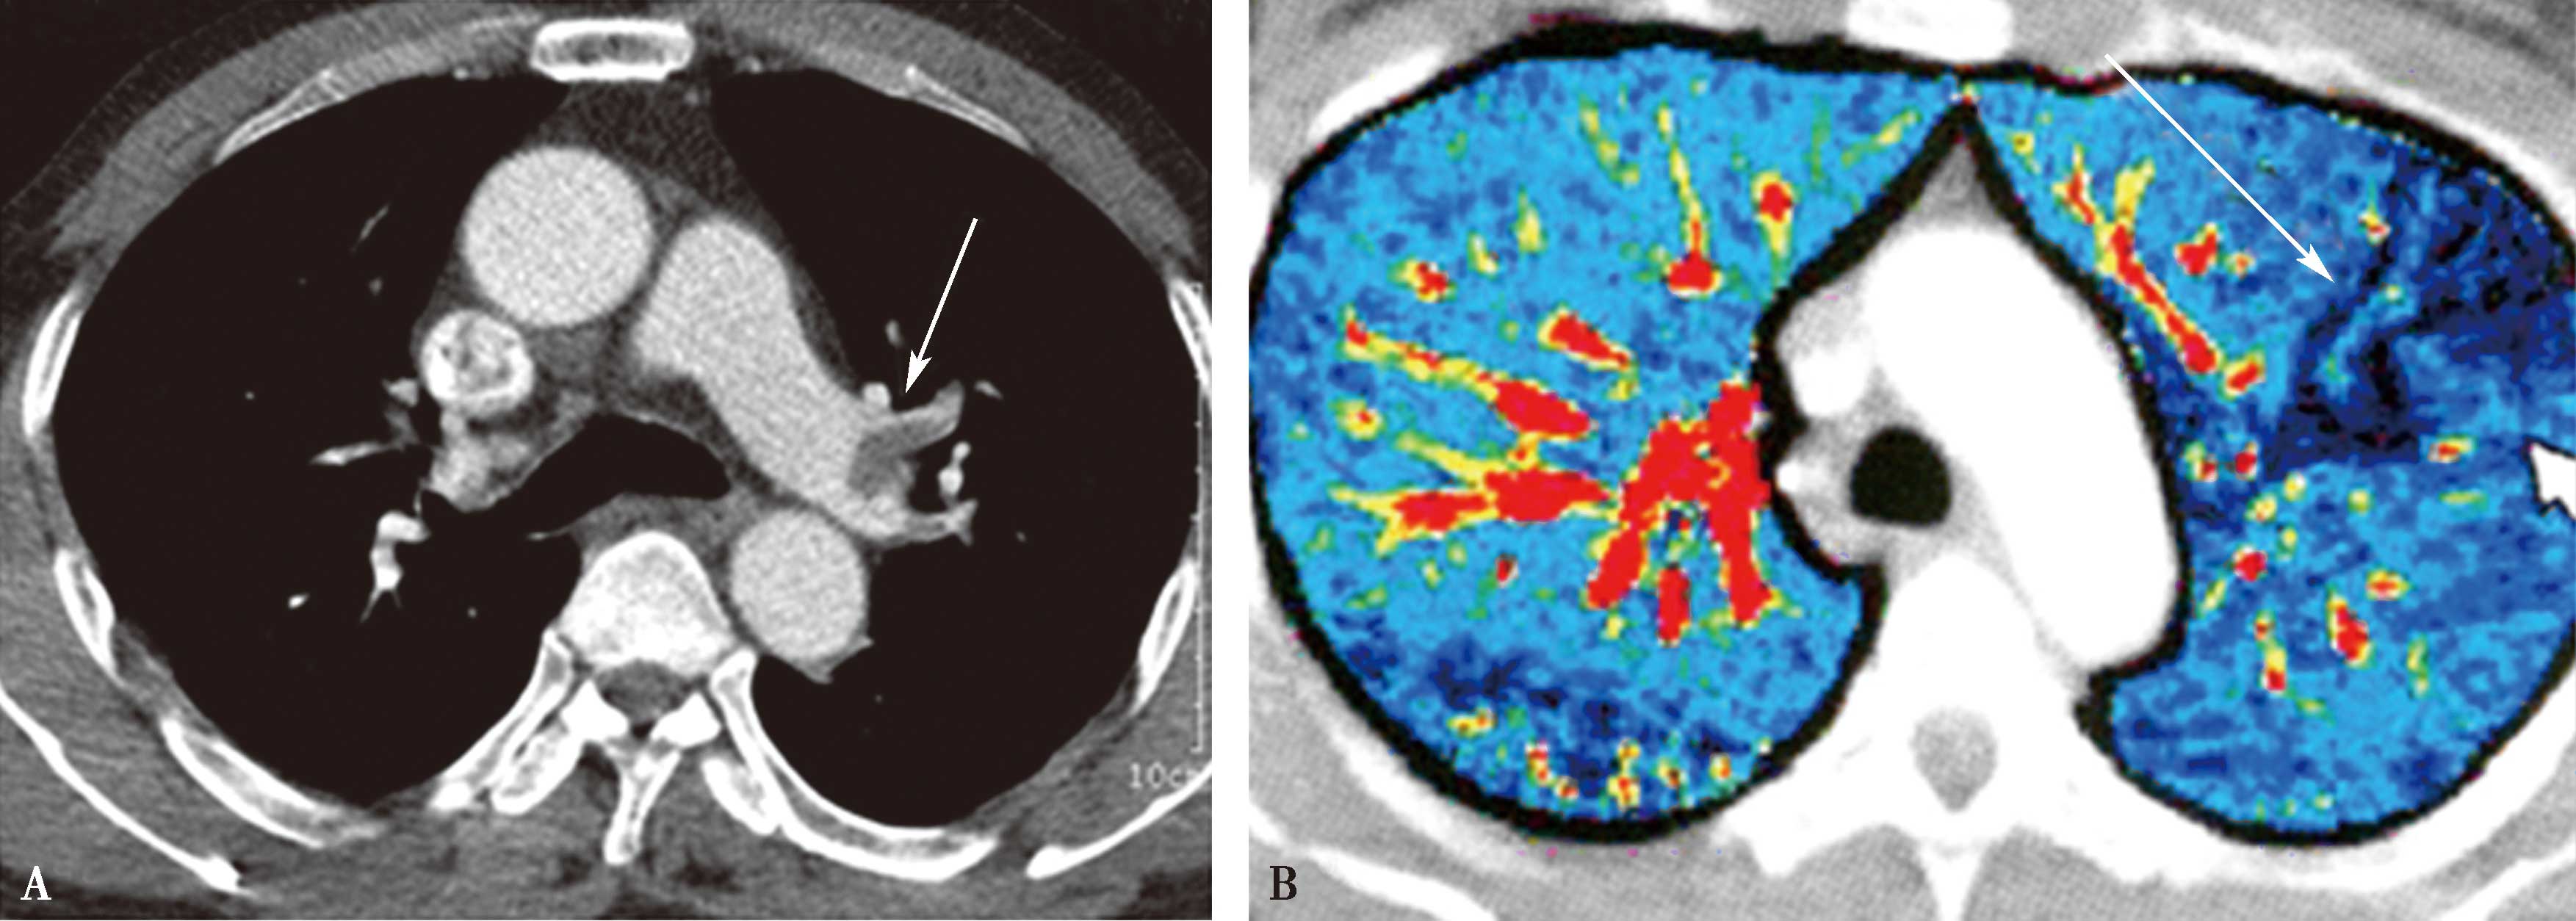

图8-3-5 肺栓塞双能CT肺灌注成像(DELPI)

CTPA显示左肺舌叶段-亚分段、下叶内前基底段-亚分段未显影(A↑),灌注扫描示相应肺段灌注缺损(B↑),明确左肺舌叶段-亚分段、下叶内前基底段-亚分段肺栓塞诊断

图8-3-6 肺栓塞双能量CT能谱成像

A.右肺下叶外基底段栓塞(↑);B.能谱成像得到肺碘基物质图,梗阻肺段呈低灌注,清楚反映栓塞分布、程度(↑)